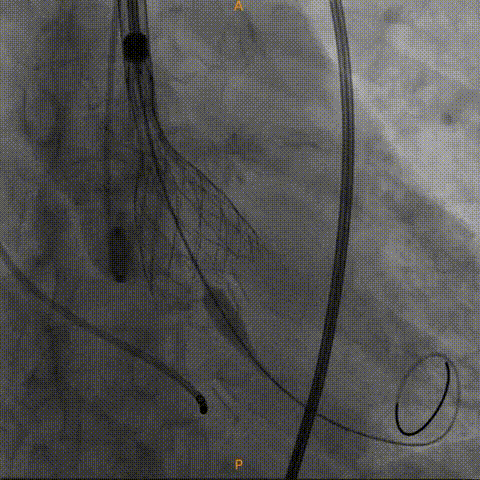

左冠造影灌注良好

右冠造影灌注良好

瓣中瓣形态良好,无反流